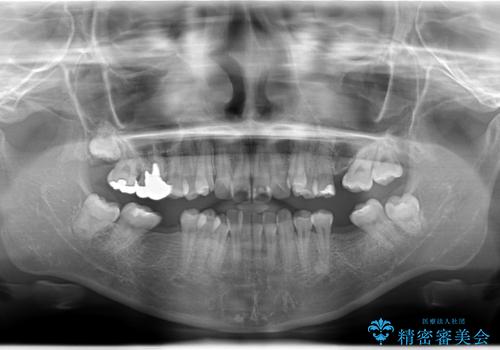

- 患者様は、下顎両側の第1大臼歯(6番)と右上6番の欠損を主訴に来院されました。

通常であればインプラントによる補綴が第一選択となる症例でしたが、患者様ご自身がインプラントを希望されなかったため、矯正治療によって欠損部の閉鎖を図る方針としました。

同時に、親知らず(智歯)の萌出や位置も考慮し、咬合全体のバランスを改善する矯正治療計画を立案しました。